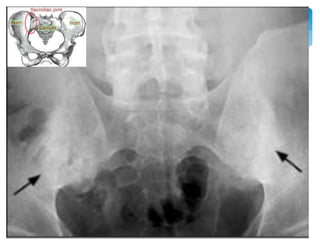

[image tool: MRI]

modified by Medscape Rheumatology education, Expanding

the spectrum for TNF antagonist: Safty & Efficacy in the

Spondyloarthropathies: Ankylosing Spondylitis

Image tool: MRI,

Ultrasound

Sacroiliitis

2~5年 Modified New York criteria 1984

1. 下背痛僵硬 休息無法減輕 三個月以上

2. 腰椎活動範圍受限

3. 擴胸範圍受限

4. X光有薦腸關節炎雙側2級或單側3級以上 4+ 1

or 2 or3